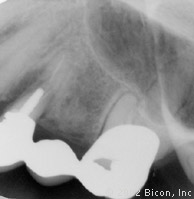

2. | X光片显示失败的根管治疗及三单位固定桥的不良修复体。 |